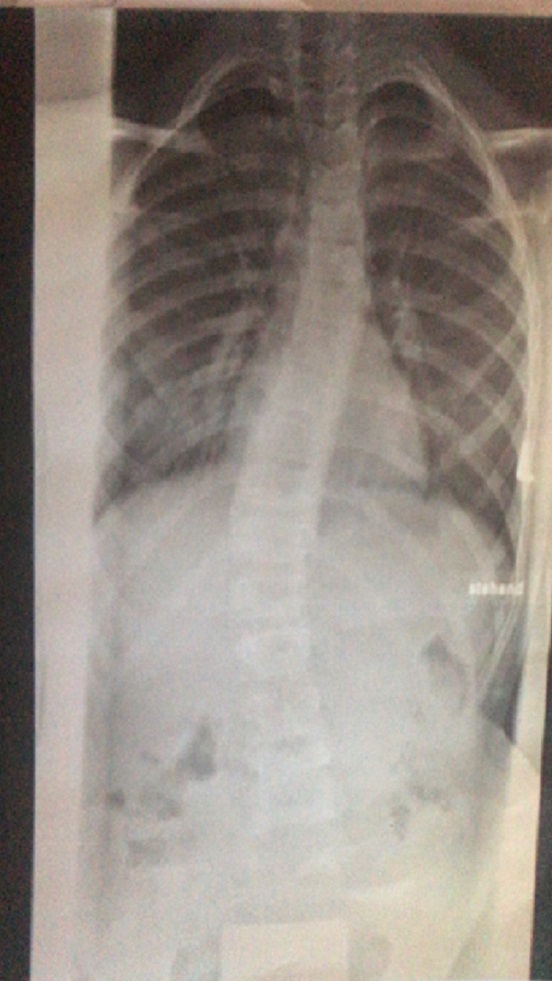

Meine Tochter hat Diagnose mit 9 Jahre alt bekommen und damals hatte sie S-Bogige Skoliose 13-15 Grad. Der Arzt sagte "beobachten" und hat Physio verschrieben. Als meine Tochter 11 geworden ist, hat sich die Krümmung wieder verschlechtert (25/26 Grad) und der Arzt hat uns das Korsett verschrieben. Wir haben lange überlegt, wo wir das Korsett machen lassen, da davon eigentlich sehr viel abhängt. Ich habe viel gelesen und vor allem sehr viel über Rahmouni Korsett - wir sind dann 300km zu Rahmouni gefahren und dort das erste Korsett bekommen. Das Bild vor Behandlung im Korsett:

Vor Behandlung 2.jpg

(142.75 KiB) Noch nie heruntergeladen